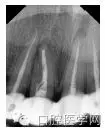

X線根尖片示:右上尖牙至左側(cè)切牙根管內(nèi)可見不連續(xù)阻射影,根管治療不嚴(yán)密,欠填,根尖處可見低密度透射影像不規(guī)則;多角度拍攝右上側(cè)切牙根尖,發(fā)現(xiàn)獨立雙根管,有遺漏細(xì)小根管內(nèi)空虛,見圖1。診斷:右上尖牙、側(cè)切牙慢性根尖周炎伴瘺口形成。

圖1 根管內(nèi)可見不連續(xù)阻射影,根充不嚴(yán)密欠填,根尖處可見低密度透射影像